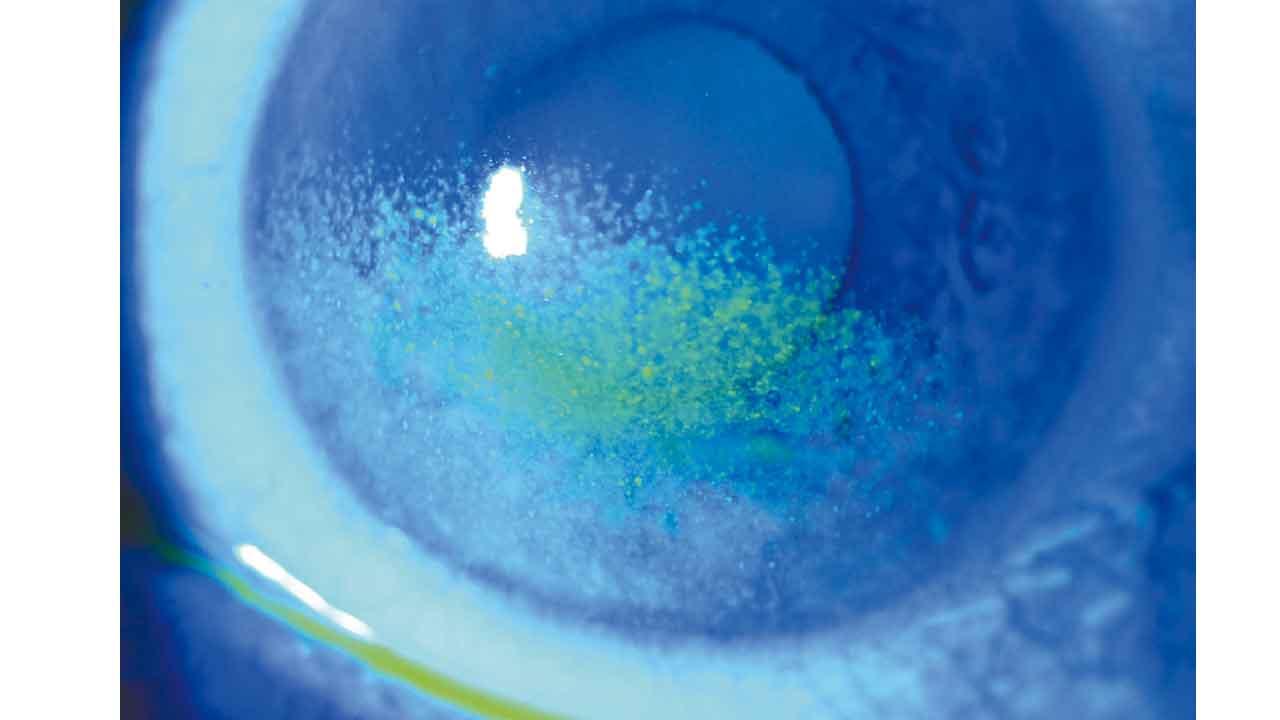

• 藥物導致眼乾

藥物導致眼乾

健康